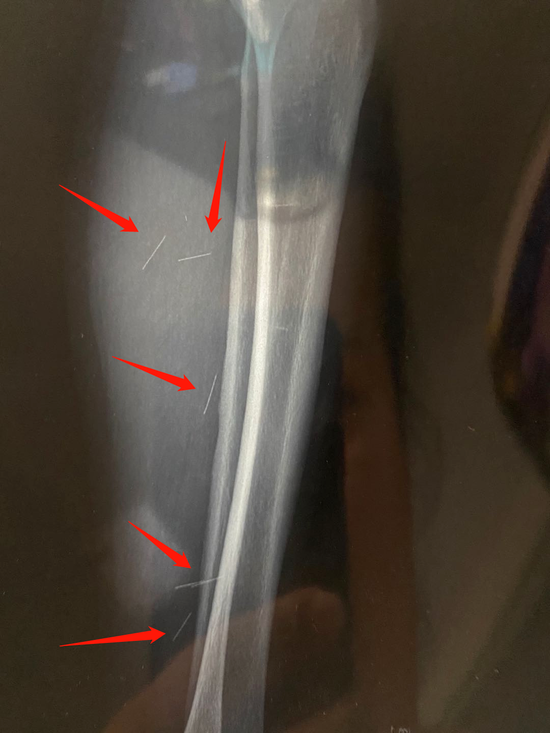

ct照片显示姜女士小腿内居然有六根断针!

图片尺寸550x733

图3:图为长有六根脚趾的x光片.

图片尺寸630x501